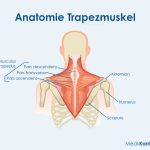

b/ Cơ liên quan:

– Cơ hoành (Diaphragma): Ảnh hưởng nhịp tim khi thở

– Cơ ức đòn chũm, liên sườn, cơ cổ trước: Căng thẳng có thể ảnh hưởng nhịp tim

(Hình ảnh đính kèm:)